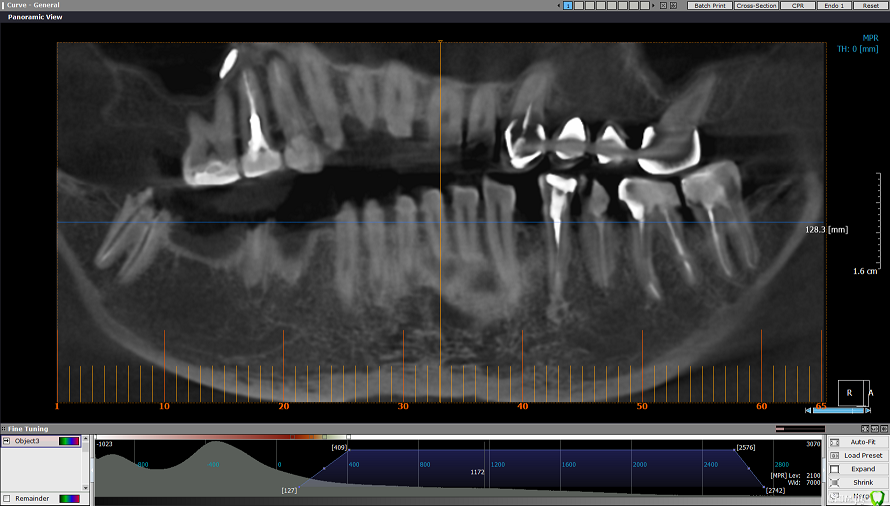

msa Опубликовано 27 февраля, 2019 Поделиться Опубликовано 27 февраля, 2019 Здравствуйте, уважаемые доктора!Прошу совета в выборе оптимального плана лечения и восстановления зубного ряда.Слева вверху (2.3-2.6) мост м/к с 1998 г(со слезами обточила здоровый красивый клык).Справа внизу был мост м/к 2006г на 4.4-4.7 (опорный моляр 4.7 + штифт в 4.5, конструкция была не очень, т.к. не отдала обтачивать под коронку клык 4.3) Через 7 лет мост слетел… От слова совсем.В н/вр пытаюсь понять, нужно ли бороться за премоляр 3.5 Или однозначно удалять? Можно ли сохранить 3.6 с помощью культевой вкладки?Какие варианты оптимального замещения низа справа 4.4-4.7? Корни пока не удаляю. Жизнеспособен ли верх 1.4-1.6? (пломбам больше 20 лет) Скриншоты из КТ от 25.02.19 ОПТГ не делалаСпасибо!С уважением, Марина Ссылка на комментарий

kramer Опубликовано 27 февраля, 2019 Поделиться Опубликовано 27 февраля, 2019 Нужна ОПТГ или панорамный срез из КТ Ссылка на комментарий

msa Опубликовано 27 февраля, 2019 Автор Поделиться Опубликовано 27 февраля, 2019 (изменено) Нужна ОПТГ или панорамный срез из КТ Получилось немного кривоватокрупно Изменено 27 февраля, 2019 пользователем msa Ссылка на комментарий

msa Опубликовано 28 февраля, 2019 Автор Поделиться Опубликовано 28 февраля, 2019 Составила одонтопародонтограмму по Курляндскому и посчитала коэффициенты силового соотношения верхних и нижних зубных рядов.Низ (14,15 из 30,0): 1,2/ 7,0/ 5,95Верх (13,8 из 30,5): 2,25/ 7,1/ 4,45 Ссылка на комментарий